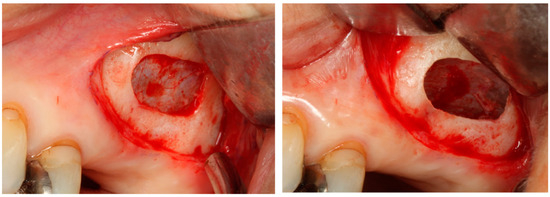

4.1. Alveolar Ridge Preservation

4.1.1. Efficacy of Alveolar Ridge Preservation and Associated Complications

4.1.2. Selection of Bone Grafting Materials in ARP